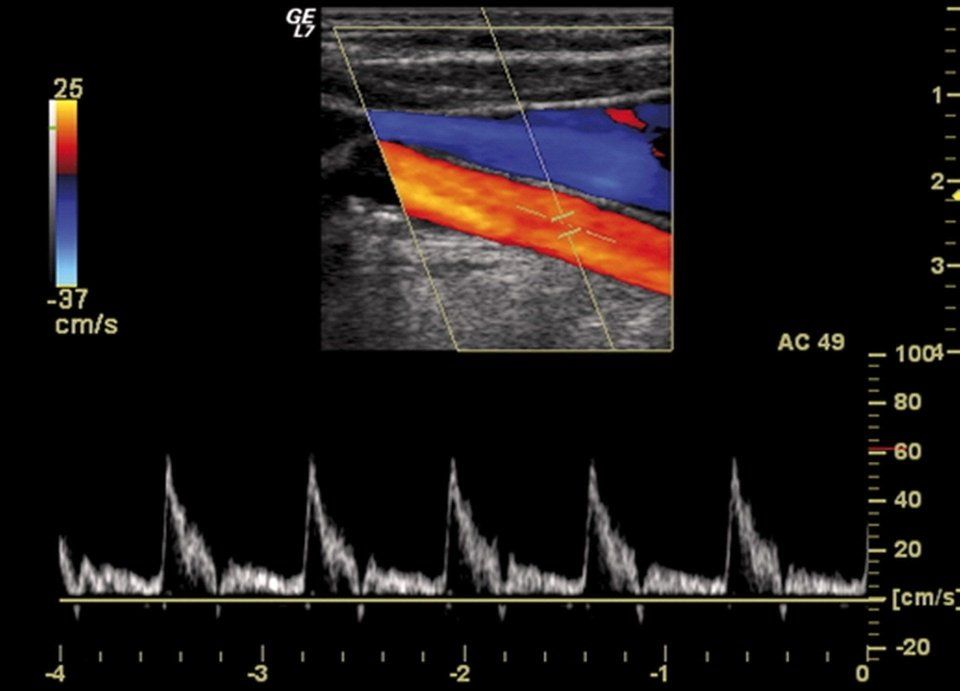

Ecocolordoppler ed ecodoppler

Attraverso l’aggiunta di un effetto doppler all’ecografia è possibile studiare lo stato e la conformazione degli organi interni in tempo reale.

Questo esame consente di evidenziare anche il circolo arterioso, venoso e la vascolarizzazione degli organi, dati essenziali per diagnosticare trombosi, varici, reflussi, restringimenti e occlusioni.